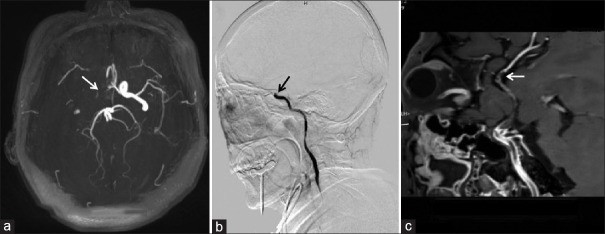

Background and purpose: Detecting the proximal occlusion site (POS) and distal boundary of the occlusion (DBO) of arterial occlusion is very important for the prognosis of endovascular treatment. Recent studies have shown that magnetic resonance imaging (MRI) and magnetic resonance angiography (MRA) are also beneficial for preoperative patient selection for endovascular therapy. High-resolution vessel wall MRI (HRVW-MRI) for intraluminal detection of arterial largevessel occlusions (LVOs) is receiving increasing attention. The purpose of this study was to evaluate the diagnostic efficacy of HRVW-MRI for POS and DBO.

Materials and methods: The data of 42 patients with acute anterior circulation cerebral infarction were retrospectively analyzed. By comparing with digital subtraction angiography (DSA), the POS and DBO were analyzed to determine the efficacy of HRVW-MRI for LVO location.

Results: Good to excellent interobserver consistency was achieved in the analysis and evaluation of all image data (k > 0.70). There was better concordance for the POS between HRMRI and DSA than that between MRA and DSA (k = 0.834 vs. k = 0.309). Compared with DSA, HRVW-MRI showed an advantage over DSA in terms of clearly determining DBO (χ² = 9.389, P < 0.01).

Conclusion: HRVW-MRI demonstrated a comparative advantage over Time-of-flight-MRA for differentiating the POS, with accuracy near-equivalent to that of DSA and a clear advantage over DSA for DBO detection. HRVW-MRI has the potential to improve preoperative planning for endovascular therapy.